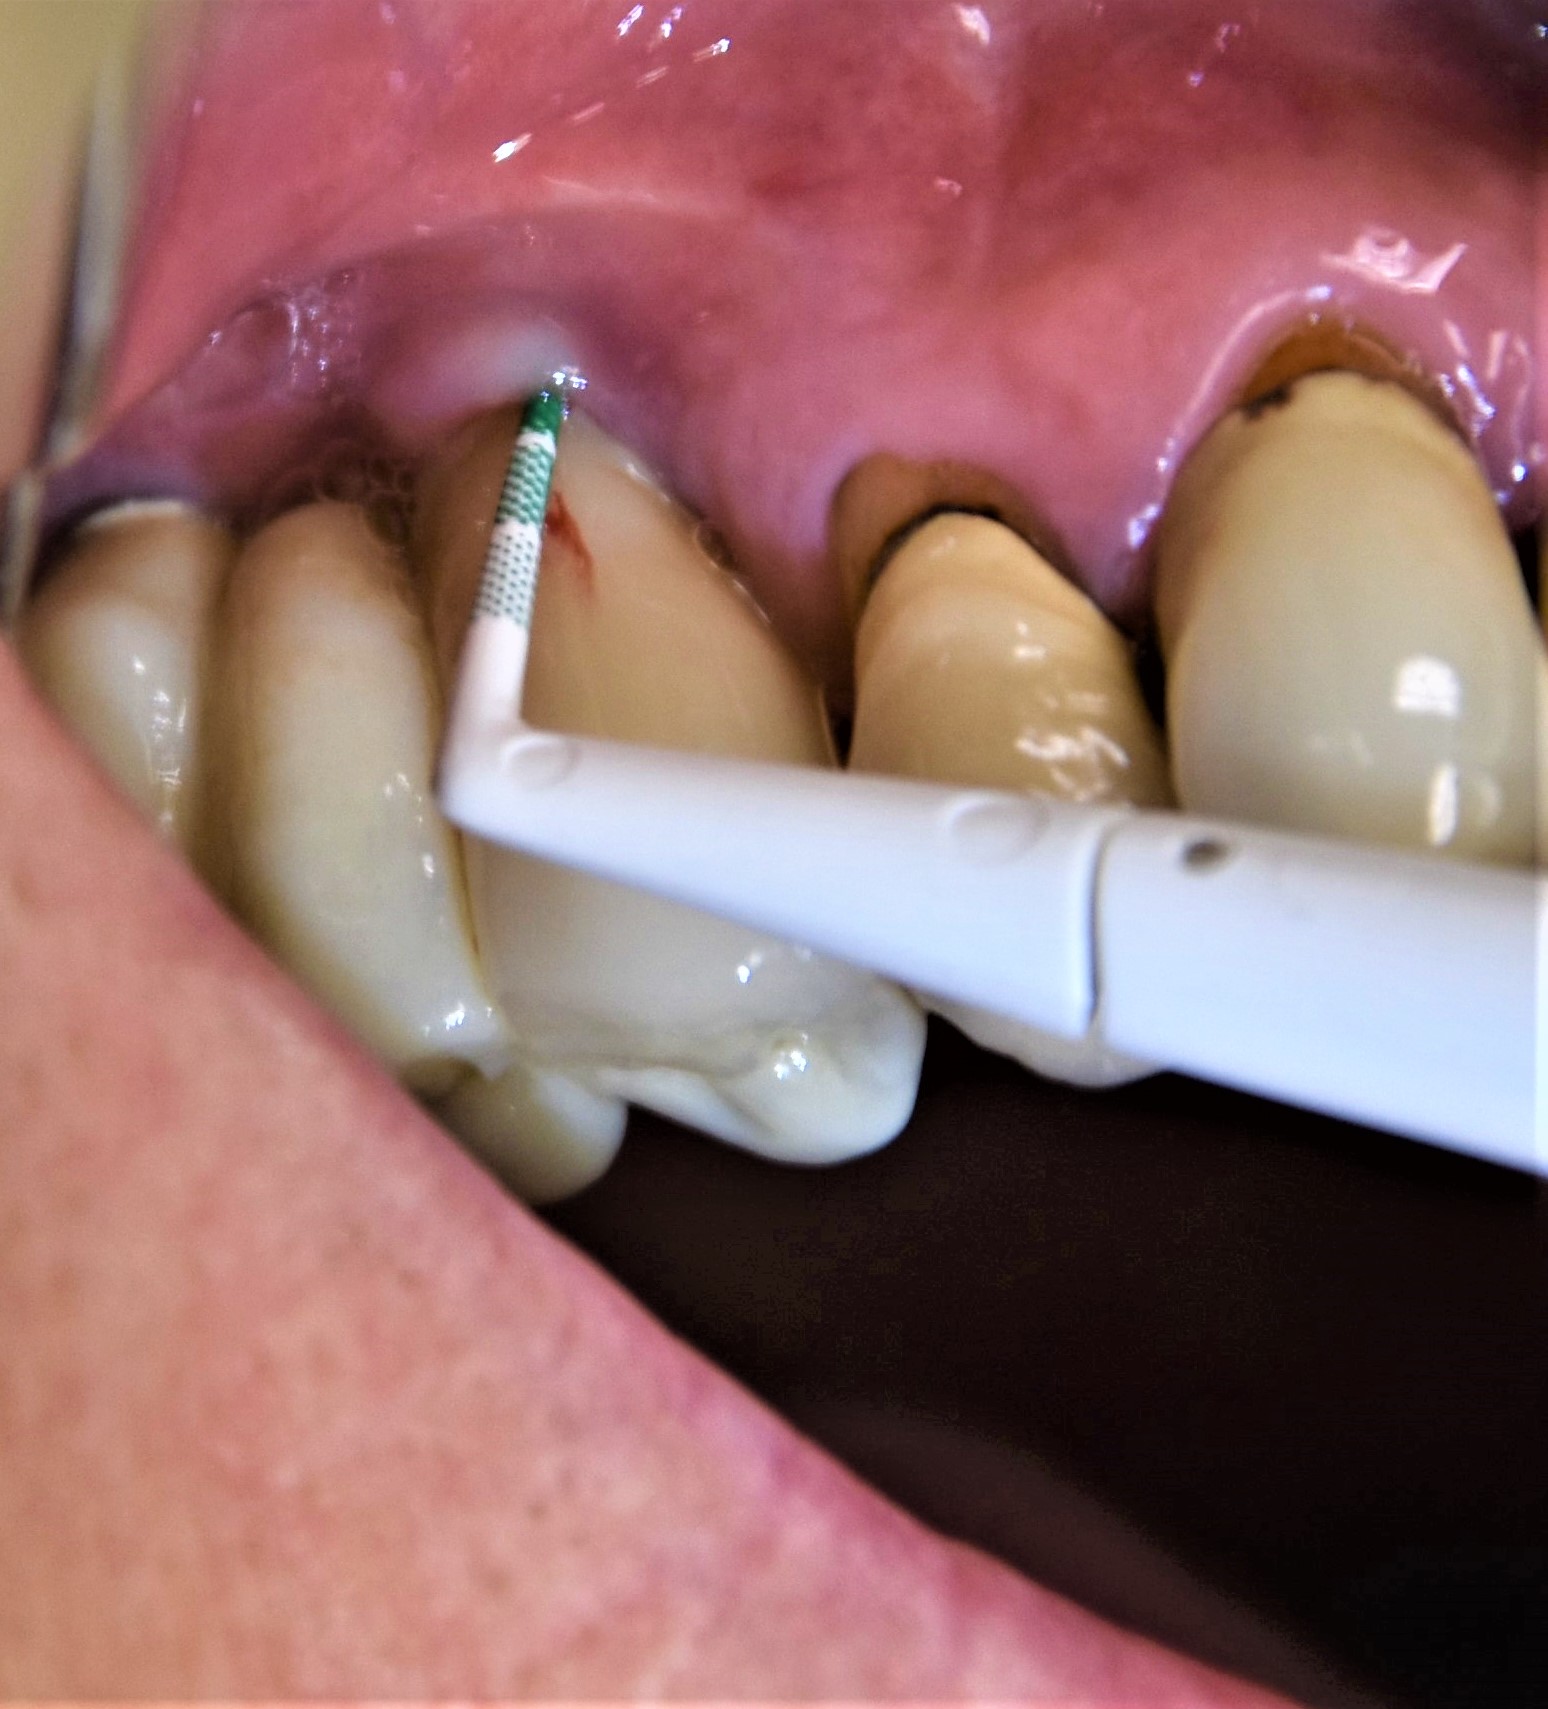

Abb. 2: Einmal jährlich sollten Taschensondiertiefen an Implantaten gemessen werden, um frühzeitig eine Periimplantitis festzustellen

Es ist von Vorteil, bereits beim Einsetzen der Suprakonstruktion die TST/BAS (6-Punkt-Messung) aufzunehmen. Der Wert dient als Baseline und sollte in der Patientenkartei festgehalten werden. Einmal jährlich empfiehlt es sich, TST/BAS an Implantaten aufzunehmen, um einen möglichen Abbau des periimplantären Stützgewebes zu ermitteln (Abb. 2). Dieser sollte mit der Baseline verglichen werden. Stellt sich eine Abweichung des Referenzwertes dar, ist es ein erster Hinweis auf einen entzündlichen Prozess. Periimplantitis kann mit weiterer Diagnostik (Röntgenbilder) im Frühstadium erkannt und behandelt werden. Laut der aktuellen Klassifikation von periimplantären Erkrankungen kann in Abwesenheit vorheriger Untersuchungsdaten die Diagnose einer Periimplantitis aufgrund der Kombination von Vorhandensein von Blutung und/oder Suppuration bei schonungsvollem Sondieren und Sondierungswerten von ≥6 mm gestellt werden (Abb. 3). Bei der Aufnahme der Sondiertiefen kann eine Kunststoffsonde durch Flexibilitätseigenschaften im Vergleich zu einer starren Stahlsonde einen Vorteil bieten (Abb. 4). Das gilt insbesondere bei Implantaten, die sich durch volumenöse Aufbauten als schwer zugänglich erweisen. Eine weitere Schwierigkeit beim Sondieren kann das Platform-Switching (Rö-Bild, Abb. 5) sein (Versorgung von Implantaten mit Durchmesser-reduziertem Aufbau). Die Sonde kann beim Messvorgang auf die Implantatschulter stoßen.